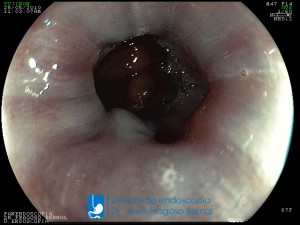

La Unidad de Endoscopía fue creada en 2002 por el Dr. Jesús Fragoso Bernal, es pionera en el estado por la utilización de la tecnología más avanzada, que nos permite ofrecer servicios integrales de diagnóstico y tratamiento para las enfermedades del aparato digestivo.

El profesionalismo de nuestro personal, altamente especializado, se distingue por la calidad y calidez de nuestros servicios con el objetivo de brindar una atención de excelencia en el ambiente más confortable para comodidad y seguridad de nuestros pacientes.

"La Unidad de Endoscopía se ha caracterizado por un progreso continuo desde su inicio marcando la pauta en los procedimientos endoscópicos en el estado de Tlaxcala y estando siempre a la vanguardia tecnológica."

Dr. Jesús Fragoso Bernal